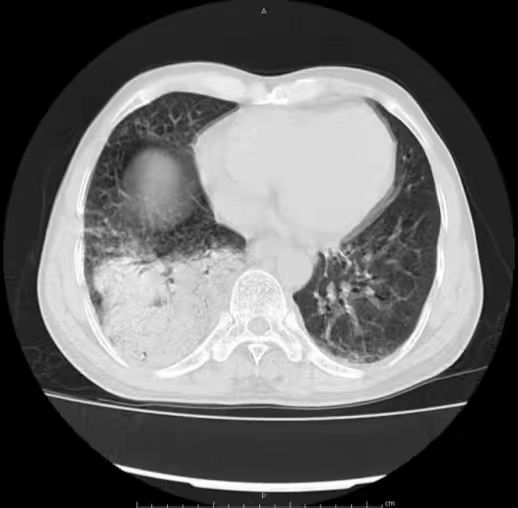

胸部 CT 如下:

肺炎链球菌肺炎多为肺泡性肺炎,少数血播肺炎链球菌肺炎好发于老年人及免疫力低下人群,PCT 明显增高。影像上,早期在血管炎的基础上仍能见到按肺小叶充填及闲置的表现(肺泡性肺炎的表现),而大片实变影已不能分辨是否为血管炎(病灶边缘磨玻璃仍可看出血管炎),在肺尖段不会占据整个层面(与铜绿假单胞菌肺炎不同),而在下肺往往表现为齐头并进的特点,分布上多上肺优势。